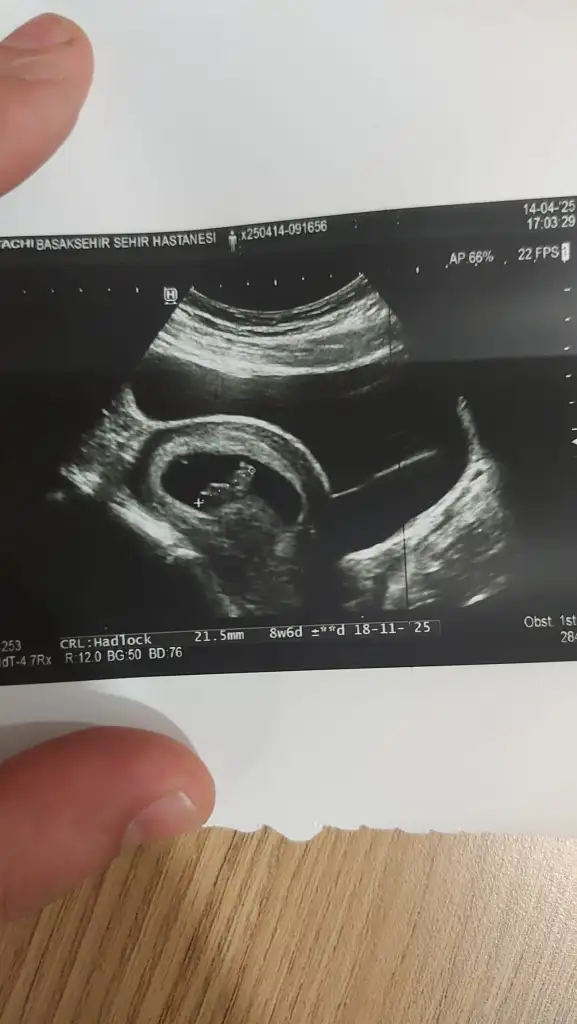

ay benimkini de yorumlar mısınız 🙏🏻 karından ultrason

• IMG_0283.webp

IMG_0283.webp

20,1 KB · Görüntüleme: 77

Bu bebiş büyümüş tahmin etmek zor ☺️ ama içimden erkek geçti 🌸